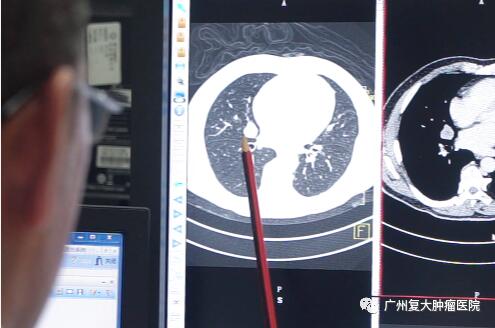

而防癌体检,是通过常规体格检查(比如用触摸的方法去寻找乳腺癌和睾丸癌的肿块)、实验室取样化验(检查血液、粪便或者其他体液,寻找肿瘤标志物),以及各种成像(各种CT、X光、MRI)等等来了解癌症发病前的状态,是早期发现癌症的重要途径。

肺部肿瘤——胸部x光。如存在重度吸烟史或合并咳嗽、咳痰、咳血等呼吸道症状时,可选择低剂量肺CT检查。